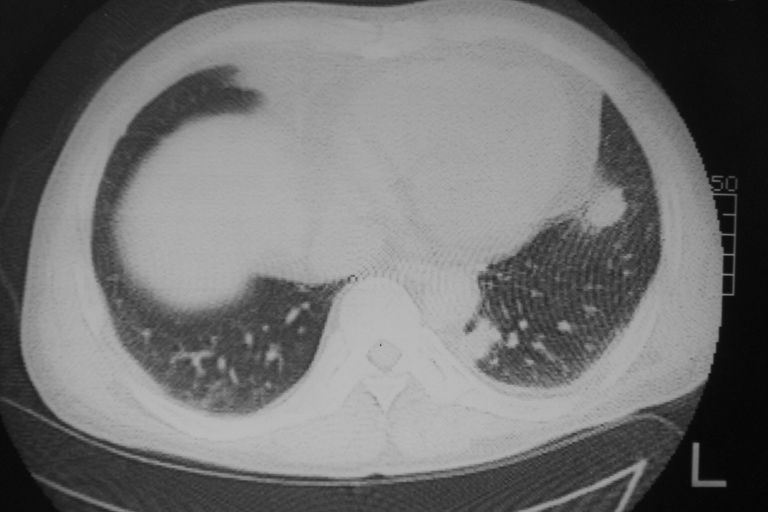

患者 男 50岁 无痛性咯血3天,无其他不适.

1 左肺下叶基底段见两结节软组织密度灶, 肺窗边缘见有毛刺征像, 不能排除占位. 2 建议结合临床治疗一周后ct随访在看其结果.

2心包积液

2、心包积液

2 心包积液。

考虑右下肺周围型肺癌,心包积液不确切,像是脂肪

左下肺结节状软组织密度影,一个边缘有卫星病灶,邻近胸膜增厚.另一个有毛刺.心影周围水样密度影环绕.考虑:

1.肺癌可能.肺tb待排.

2.左侧胸膜增厚.心包积液.